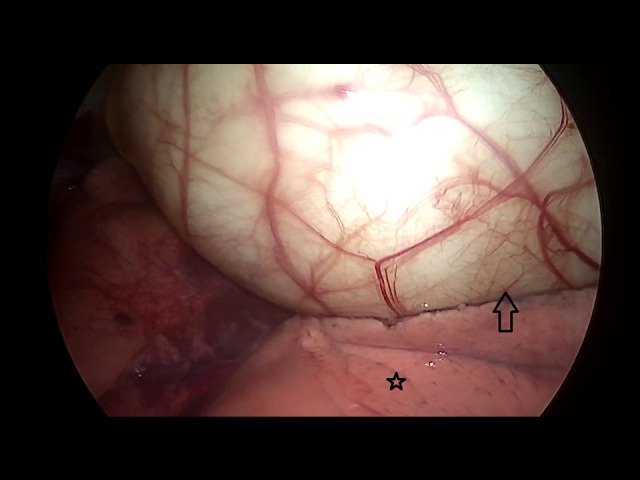

背景:包虫病仍然是一个主要的临床问题,特别是在流行包虫病的地区。这种寄生虫感染是由棘球绦虫引起的。肝和肺是受影响最严重的器官。尽管肺是最常见的胸内脏器,但肺外的胸内包虫病并不常见。然而,原发性纵隔包虫病是一种罕见的疾病,而胸腺的原发性包虫病更是极为罕见。尽管视频胸腔镜手术在胸外科领域发挥着重要作用,但其在治疗胸部包虫病中的作用尚不明确。本文报告一例17岁男性胸腔镜下胸腺包虫病原发治疗。病例报告一名17岁男性因胸闷、呼吸短促3个月前来就诊。胸片上可见明显的混浊。随后的计算机断层扫描(CT)显示在左半胸有一个大的、界限明确的囊性病变,尺寸为6.5×7×11 cm。他后来被安排进行VATS手术切除囊肿,发现囊肿与胸腺有连续性。整体胸腺切除术,以确保完全切除膀胱周围。结论:该病例的独特之处不仅在于它描述了一种罕见的包虫病部位,还在于所采用的切除技术。根据我们的文献回顾,这是最早报道的通过胸腔镜切除该部位包虫病的病例之一。此外,与开胸手术相比,VATS恢复更快,术后疼痛减轻,在类似病例中的应用有待进一步探讨。

BACKGROUND Hydatid disease remains a major clinical concern, particularly in regions where it is endemic. This parasitic infection is caused by Echinococcus species. The liver and lungs are the most affected organs. Although the lungs are the most commonly affected intrathoracic organ, extrapulmonary intrathoracic hydatid disease is uncommon. However, primary mediastinal hydatid disease is a rare entity, and a primary hydatid cyst in the thymus is extremely rare. Although video-assisted thoracoscopic surgery (VATS) plays an important role in the field of thoracic surgery, its role in treating hydatid disease in the chest is not well established. This report describes a case of 17-year-old male presenting with primary hydatid cyst of the thymus treated thoracoscopically. CASE REPORT A 17-year-old male presented to our clinic with chest tightness and shortness of breath of 3 months duration. A well-defined opacity was identified on chest radiography. Subsequent computed tomography (CT) revealed a large, well-defined cystic lesion in the left hemithorax, measuring 6.5×7×11 cm. He was later scheduled for VATS to resect the cyst, which was found to be in continuity with the thymic gland. An en bloc thymectomy was performed to ensure complete peri-cystectomy. CONCLUSIONS This case is unique not only because it describes a rare location of hydatid disease, but also due to the technique of resection that was used. Based on our literature review, this is among the earliest reported cases of a hydatid cyst in this location resected via thoracoscopy. Furthermore, compared with thoracotomy, VATS offers faster recovery and reduced postoperative pain, and its application in similar cases should be further explored.